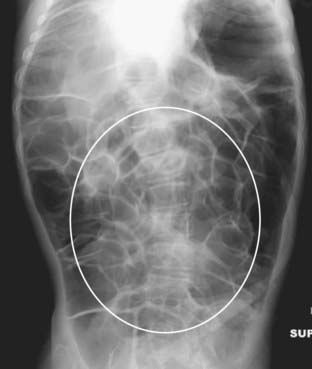

Figure 13-19 Calcified rib cartilages.

Calcification of the rib cartilages (white circle) occurs with advancing age and, while not a true abdominal calcification, can sometimes be confused for calculi when it overlies the kidney or region of the gallbladder. Calcified cartilage tends to have an amorphous, mottled appearance. Calcified rib cartilages will occur along an arc corresponding to the sweep of the anterior ribs as they turn back toward the sternum.